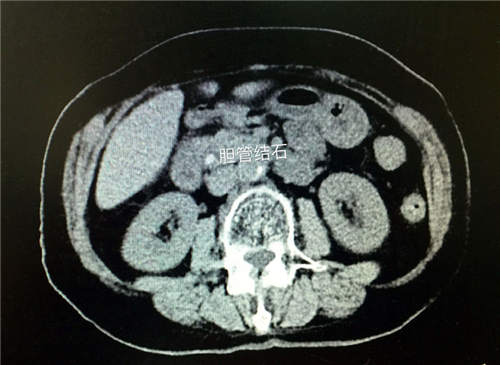

已经94岁高龄的李奶奶,一直都是小区里的“乐天派”,不料,却被几块暗里使坏的“小石头”多番搅扰,痛苦不堪。北京燕化医院确诊为胆总管结石。

通过在患者上腹部打3-4个各约5-10mm的小孔,在腹腔镜的辅助下,先小心翼翼的切开胆总管,然后置入胆道镜,发现胆总管内有大小约1.0×0.8cm左右结石数枚。用胆道镜一粒粒仔细取出,观察见胆汁排出通畅,然后用盐水清洗胆道,确认没有结石残留后,用可吸收线对胆总管进行细致的一期缝合。手术历时3小时,术中出血量仅50ml。术后一日李奶奶便下床活动并进食,恢复非常快。